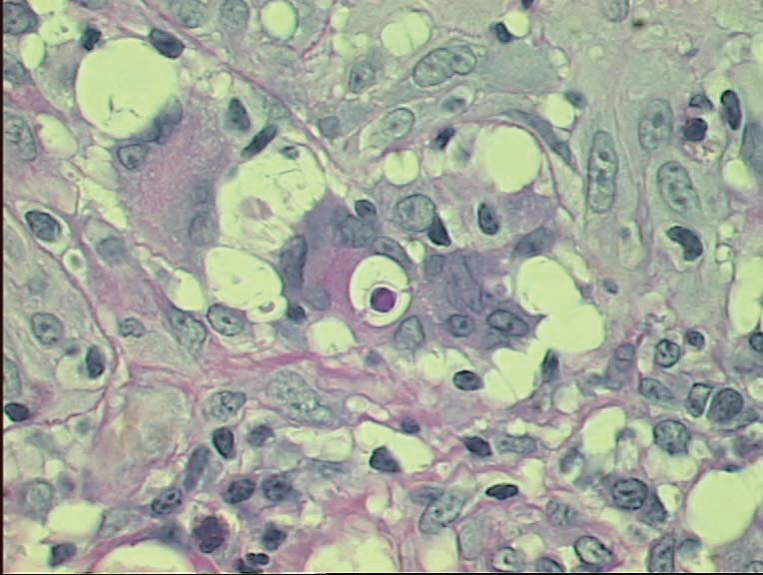

10- Paracoccidioides brasiliensis

Histopatológico